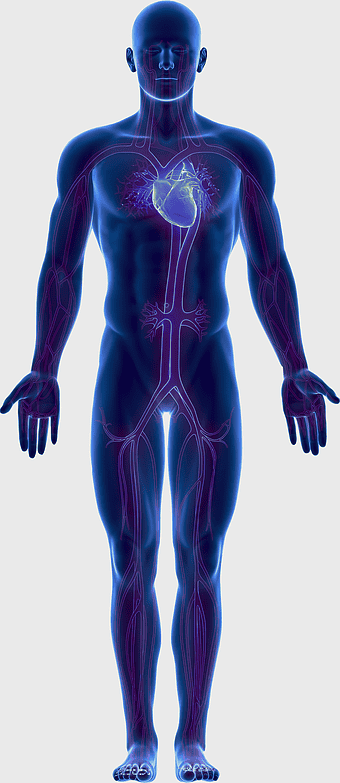

human circulatory system, blood vessel anatomy, weight loss exercise benefits, heart and artery health, vascular network visualization, cardiovascular health illustration, systemic circulation diagram -

circulatory system diagram, human cardiovascular anatomy, blood vessel network, heart circulation, systemic circulation, venous system, arterial pathways -

human heart diagram, cardiovascular system anatomy, blood vessel chart, free body diagram, circulatory system illustration, medical organ visualization, human anatomy study -

blue human anatomy illustration, human circulatory system diagram, digital human skeleton image, electric blue medical figure, human nervous system visualization, human body organ map, human health care graphic -